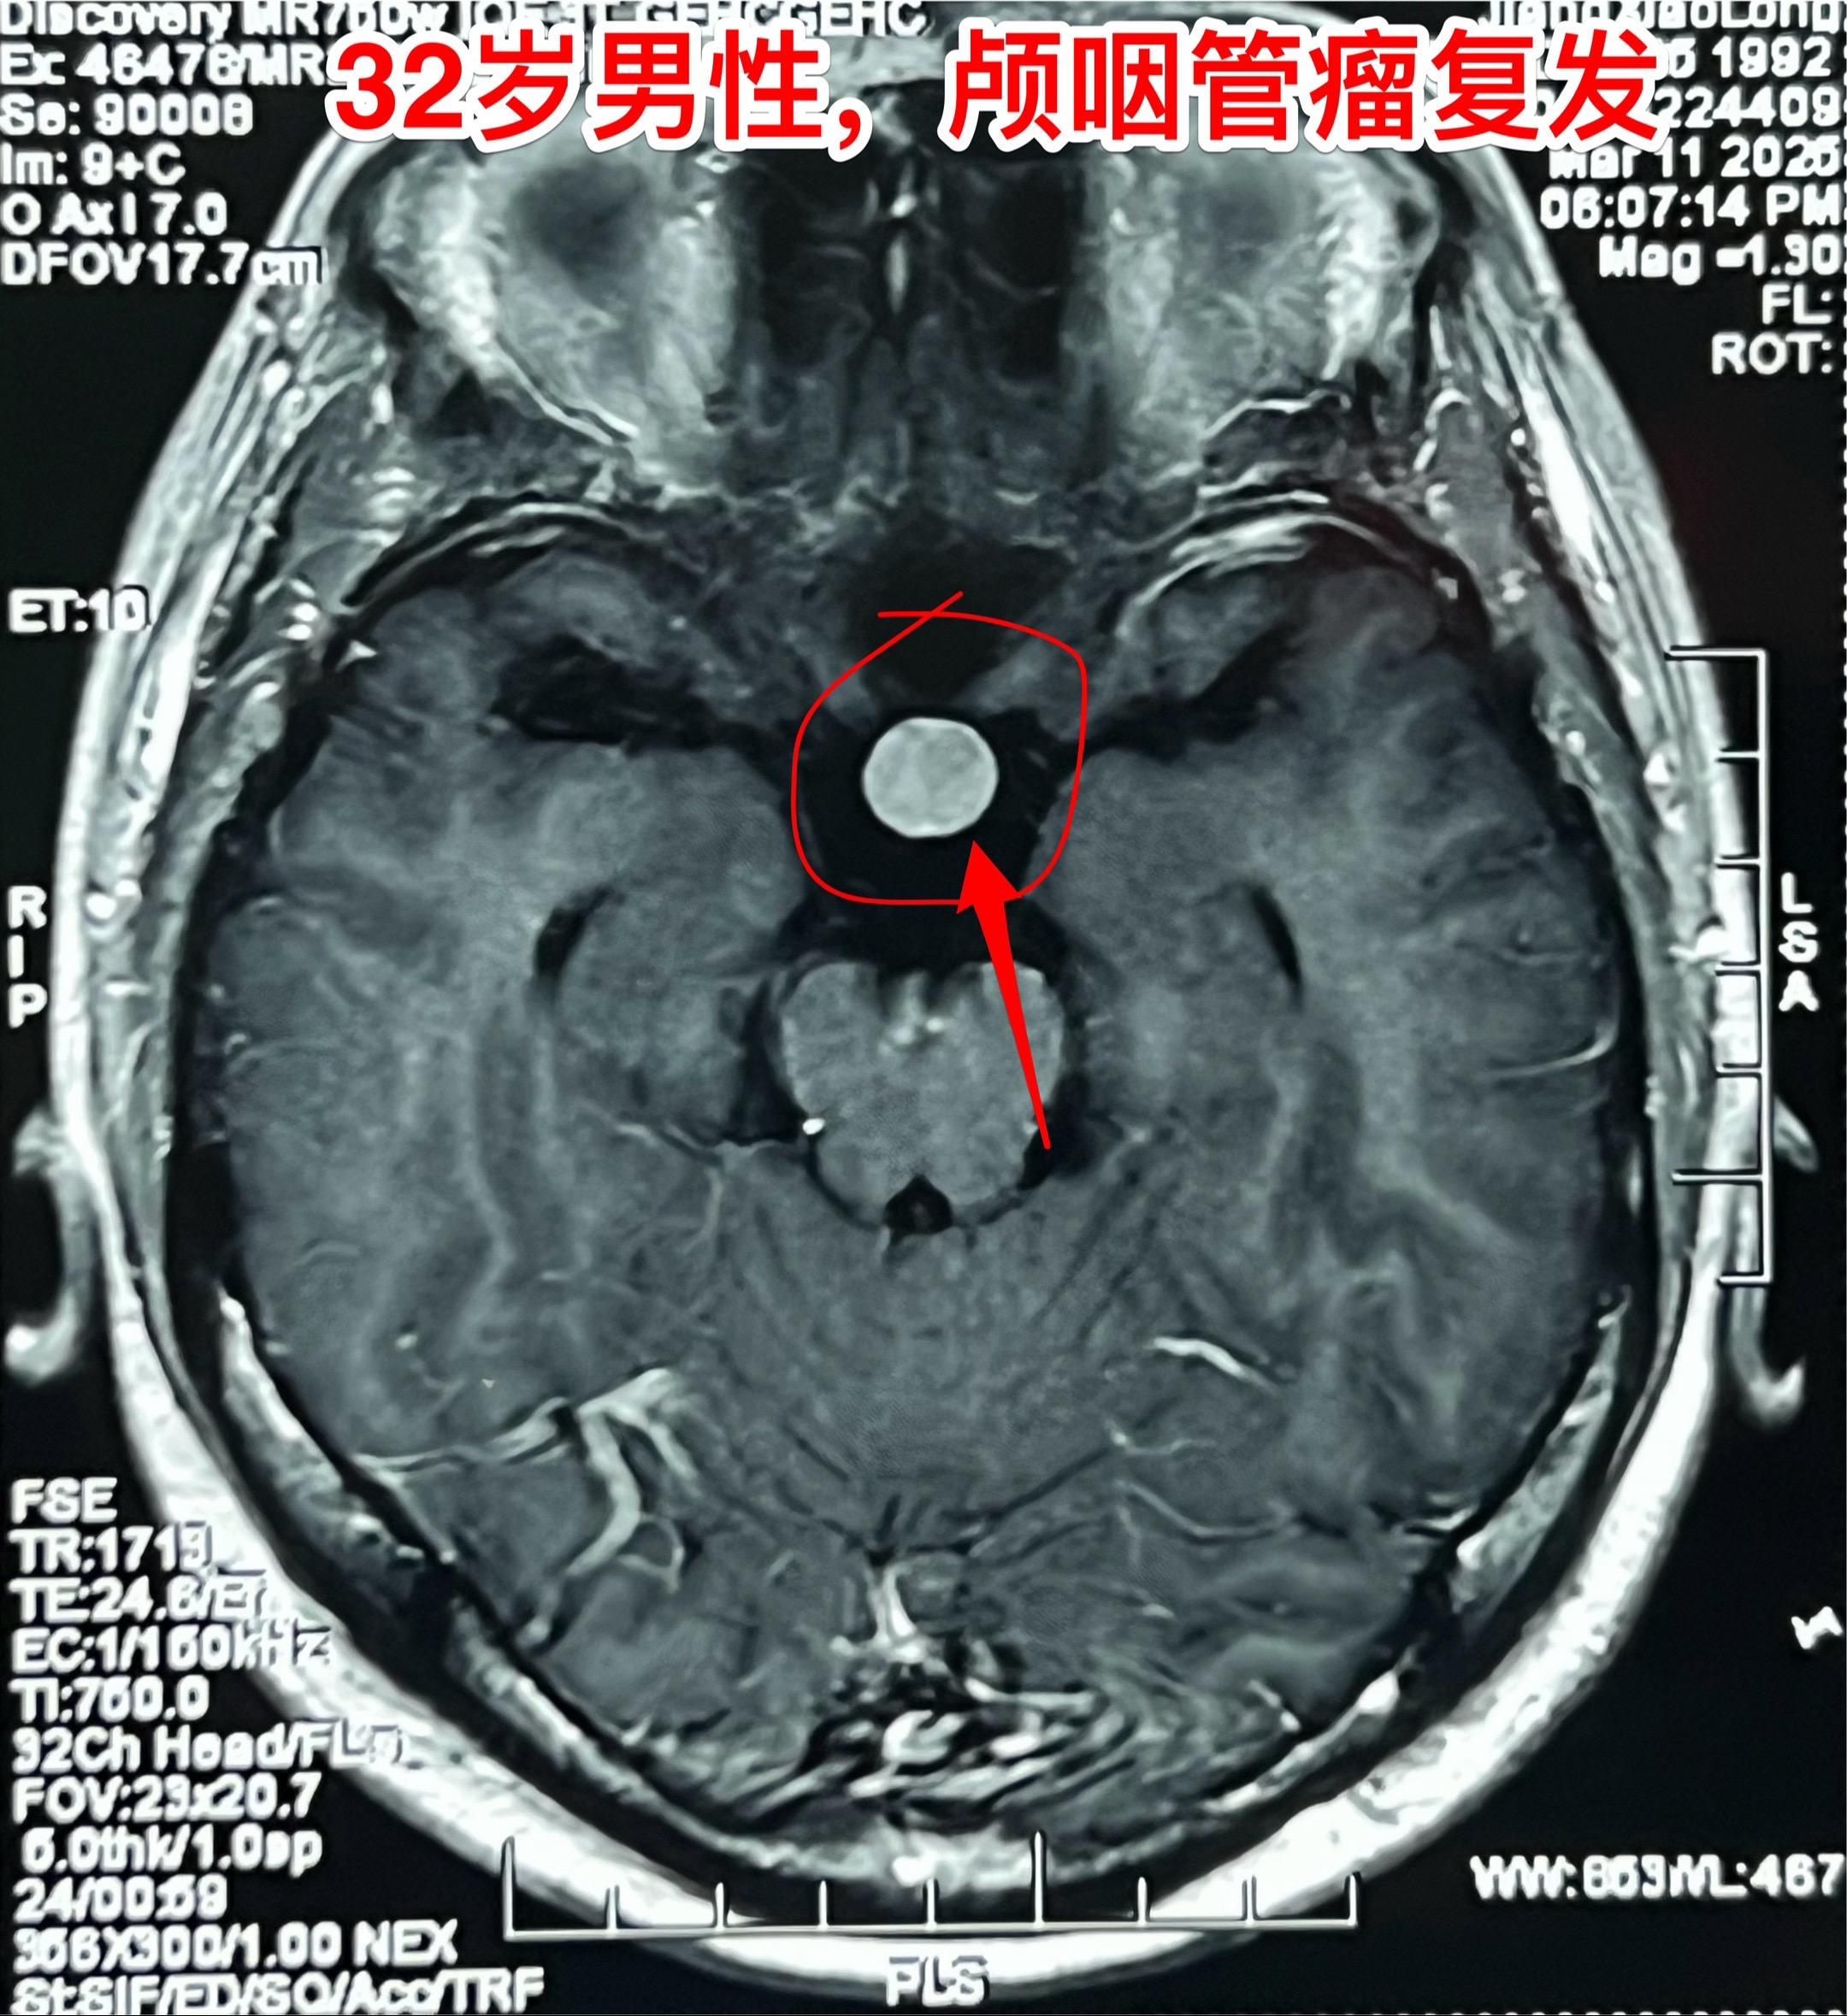

3月28日两个颅咽管瘤手术 两个都是经鼻手术手术后复发的颅咽管瘤手术。我采用了开颅手术。 第一个是64岁山西人,颅咽管瘤手术后再次出现视力下降,复查磁共振显示肿瘤复发。肿瘤是囊性乳头型颅咽管瘤,没有钙化。 第二个是32岁的湖南小伙。肿瘤有钙化。 今年春节后我科颅咽管瘤中经鼻手术后复发的病人比例明显升高了。与近十年经鼻内镜手术广泛开展是有关系。 无论是哪种手术方案,只有效果好、复发率低,病人才会满意。